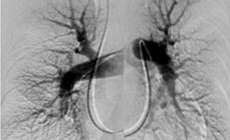

慢性血栓塞栓性肺高血圧症